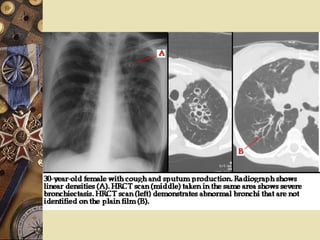

Evaluation CT or HRCT:   high sensitivity and specificity Train track sign:   the bronchial wall is thicken and visible; the bronchi lose the trend of narrowing from proximal end to distal end.

Evaluation CT or HRCT:   high sensitivity and specificity Diamond ring sign:  dilated bronchi appear as ring structures with internal diameters greater than those of their accompany pulmonary artery branches.

Evaluation CT orHRCT: high sensitivity and specificity Train track sign: the bronchial wall is thicken and visible; the bronchi lose the trend of narrowing from proximal end to distal end.

Evaluation CT orHRCT: high sensitivity and specificity Diamond ring sign: dilated bronchi appear as ring structures with internal diameters greater than those of their accompany pulmonary artery branches.